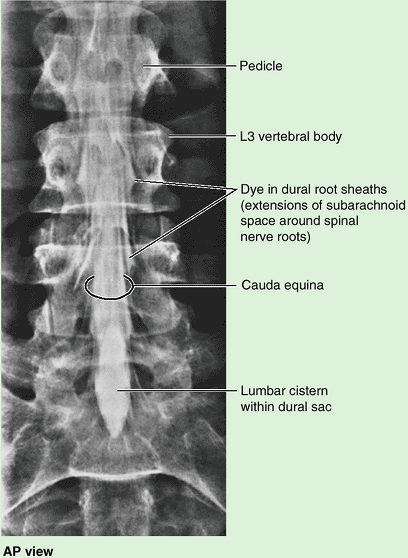

(L. horse tail), that descend past the termination of the spinal cord.

On the pelvic and posterior surfaces of the sacrum between its

vertebral components are typically four pairs of sacral foramina for the exit of the posterior and anterior rami of the spinal nerves (Fig. 4.5A & B). The anterior (pelvic) sacral foramina are larger than the posterior (dorsal) ones.

formed by the superior surface of the S1 vertebra. Its superior

articular processes articulate with the inferior articular processes of

the L5 vertebra. The anterior projecting edge of the body of the S1

vertebra is the sacral promontory (L. mountain ridge), an important obstetrical landmark (see Chapter 3). The apex of the sacrum, its

tapering inferior end, has an oval facet for articulation with the coccyx.